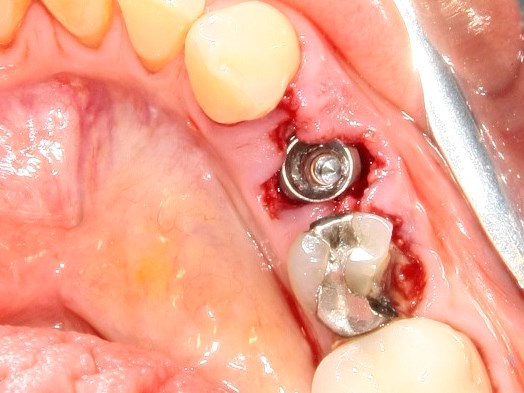

Немедленная имплантация — оптимальное решение в любой клинической ситуации